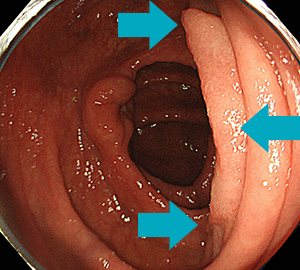

通常光(白色光)観察ではややはっきりしないポリープですが…

NBI観察によって明瞭化し…

さらに拡大機能を併用することで詳細に観察することができます。これらの機器を併用して経験豊富な内視鏡医が丁寧に挿入・観察を行うことにより、皆さまに快適・迅速かつハイクオリティーな大腸内視鏡検査(大腸カメラ/下部消化管内視鏡検査)をお受けいただける体制となっております。

大腸腺腫(右はNBI併用拡大観察像)